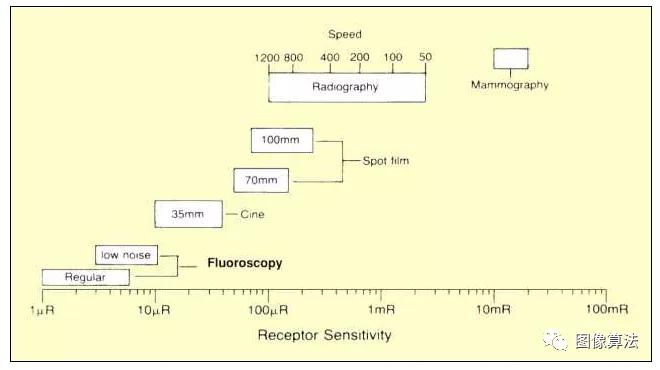

受体灵敏度

形成图像所需的光子浓度或曝光由受体的灵敏度决定 。X射线投影成像(放射摄影和荧光透视)中使用的受体的灵敏度在相当大的范围内变化,如下图所示。此图表显示了用于特定成像应用的近似值。

X射线成像中使用的受体灵敏度值

透视

常规荧光镜的受体灵敏度通常在每个图像帧的1μR至10μR的范围内。这种相对低的曝光产生具有相当大量子噪声的图像 然而,在正常的荧光透视观察中,我们一次看不到一个图像帧而是几个帧的平均值,如下所述。

一些荧光透视系统可以切换到低噪声模式,这将提高低对比度细节的可见性。在低噪声模式中,受体灵敏度降低,并且形成图像需要更多曝光。这通常称为HLC或高级控制。